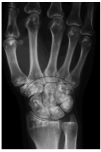

En una radiografía simple de caderas y miembros superiores se encontraron lesiones escleróticas de osteopoiquilosis en muñecas y pelvis (fig. 3). En el estudio radiológico efectuado a los padres y hermanos del paciente se hallaron lesiones óseas escleróticas en la madre, en las manos (fig. 4) y miembros inferiores.

Fig. 4.--Lesiones óseas escleróticas en muñeca y mano de la madre del paciente.